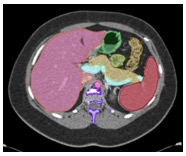

Multi-Organ Segmentation We have developed algorithms that can achieve >85% accuracy in segmentation of major abdominal organs ![]() Wang Y et al. arXiv:1804.08414. |

Multi-Organ Segmentation Multi-organ segmentation (n = 575): ![]() Wang Y et al. arXiv:1804.08414. Kawamoto S et al. [Submitted] |

Multi-Organ Segmentation

![]() Wang Y et al. arXiv:1804.08414. |